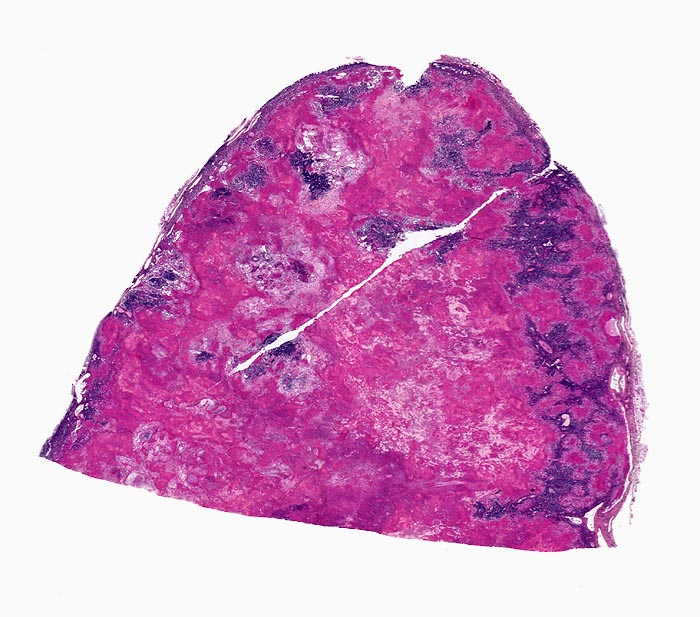

• Lymphknoten mit ausgedehnten konfluierenden eosinophilen Nekrosezonen und nur wenig erhaltenem Lymphknotengewebe (blau).

• In den grösseren Nekrosearealen sind Kerntrümmer von neutrophilen Granulozyten erkennbar.

• Demarkierung der Nekroseareale durch schlanke Epitheloidzellen, Riesenzellen vom Langhanstyp mit hufeisenförmig angeordneten Kernen und Lymphozyten.